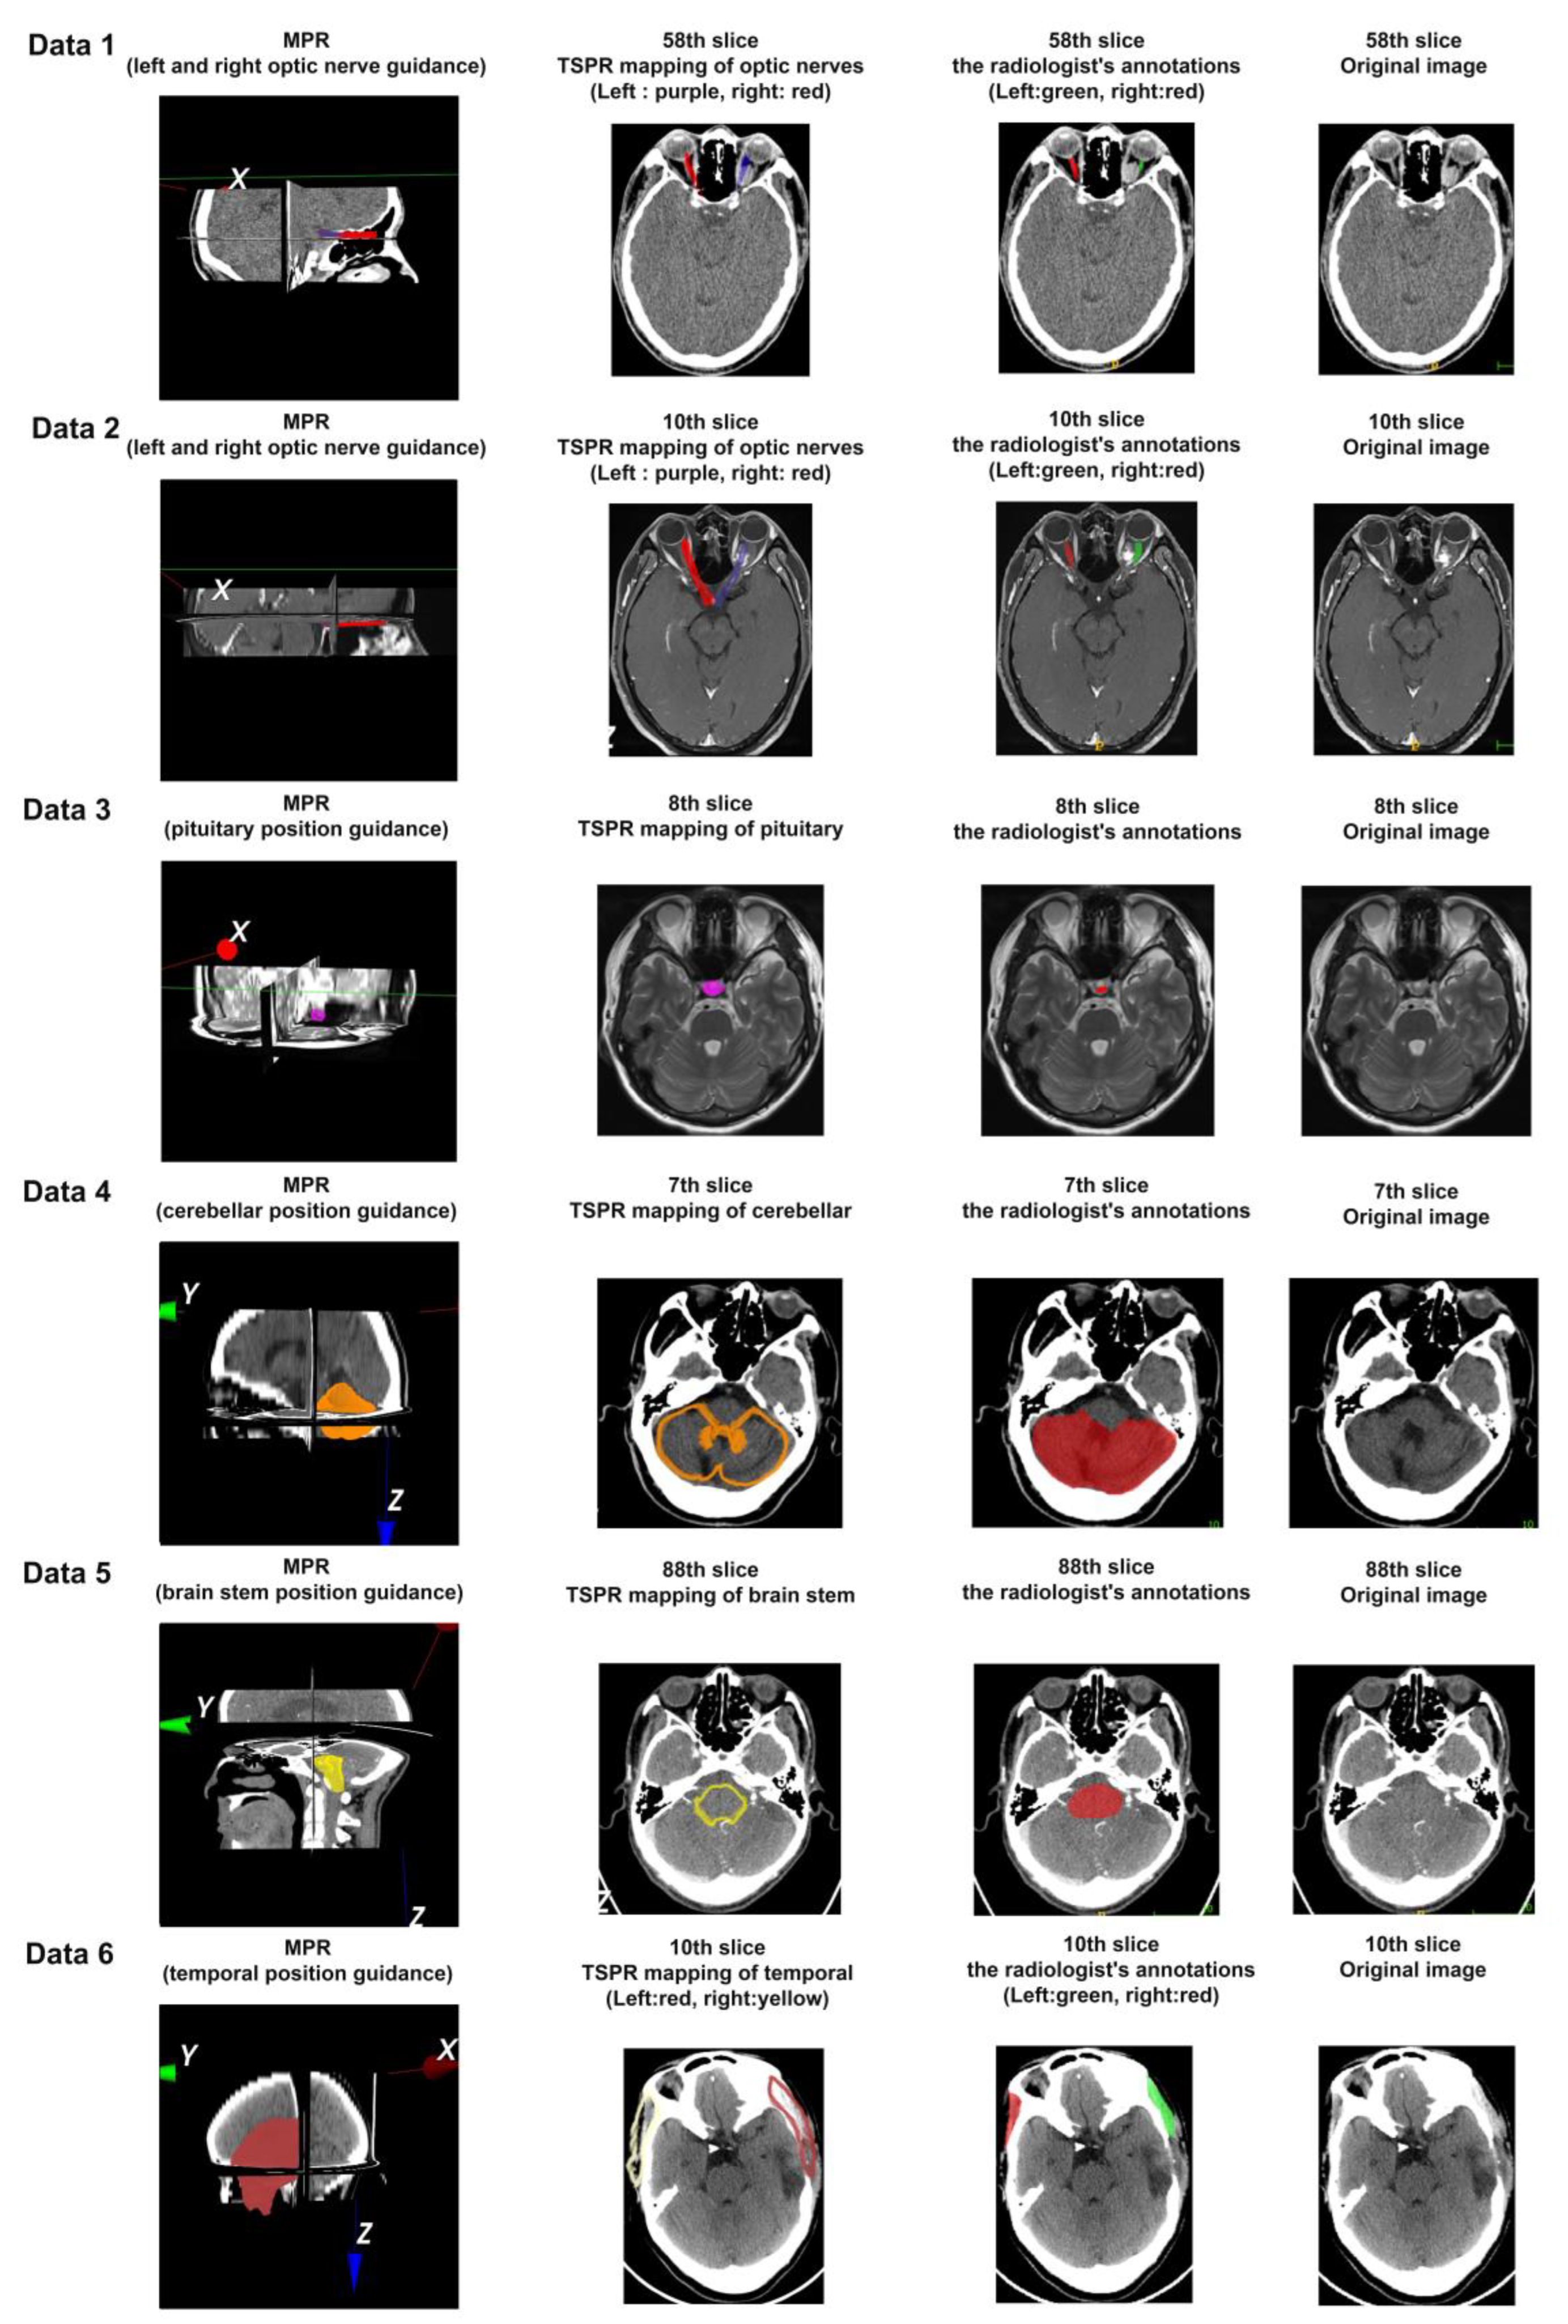

3.2. Registration Effect of Clinical Data and CVH

| Modality | Parameter | MPR of Scan Range | |

|---|---|---|---|

| Data 1 | CT | Slice Spatial Resolution: 512 × 512 Slice Quantity: 121 Pixel Spacing: 0.4336 mm\0.4336 mm Thickness: 1.0 mm ROI from radiological description: An oval-shaped nodular shadow can be seen on the inner side of the left optic nerve behind the orbital ball, suspected to be a hemangioma | ![]() |

| Data 2 | MRI | Slice Spatial Resolution: 288 × 384 Slice Quantity: 18 Pixel Spacing: 0.625 mm\0.625 mm Thickness: 3.0 mm ROI from radiological description: An oval-shaped nodular shadow can be seen on the inner side of the left optic nerve behind the orbital ball, suspected to be a hemangioma | ![]() |

| Data 3 | MRI | Slice Spatial Resolution: 512 × 512 Slice Quantity: 15 Pixel Spacing: 0.4296875 mm\0.4296875 mm Thickness: 3.5 mm ROI from radiological description: Nodular shadow on the left side of the saddle area, considering the possibility of pituitary adenoma | ![]() |

| Data 4 | CT | Slice Spatial Resolution: 512 × 512 Slice Quantity: 25 Pixel Spacing: 0.430 mm\0.430 mm Thickness: 5 mm ROI from radiological description: postoperative cerebellar changes, abnormal structural disturbances in the cerebellar region, occipital bone showing postoperative changes | ![]() |

| Data 5 | CT | Slice Spatial Resolution: 512 × 512 Slice Quantity: 177 Pixel Spacing: 0.401 mm\0.401 mm Thickness: 1 mm ROI from radiological description: cerebral softening foci in the left part of the brainstem, demyelinating changes in the cerebral white matter | ![]() |

| Data 6 | CT | Slice Spatial Resolution: 512 × 512 Slice Quantity: 30 Pixel Spacing: 0.46289 mm\0.46289 mm Thickness: 5 mm ROI from radiological description: large area of bone defect in the left temporoparietal bone adjacent to the left temporalis muscle, edema in the left temporoparietal lobe of the brain, formation of softening lesions, and slight swelling of the temporalis muscle. | ![]() |